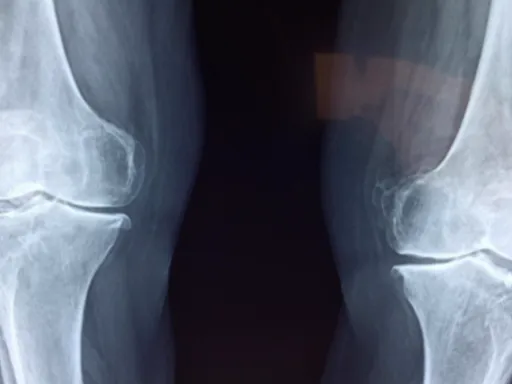

관절염과 퇴행성 변화

나이가 들면서 무릎이나 고관절에 퇴행성 관절염이 생기면 다리 통증이 나타나요. 연골이 닳아 없어지면서 뼈끼리 부딪히고 염증이 생기는 건데요. 특히 계단을 오르내리거나 오래 걸을 때 시큰거리는 통증이 느껴진답니다. 비만도 관절에 큰 부담을 줘서 통증을 악화시킬 수 있으니, 체중 관리도 아주 중요하다고 말씀드리고 싶어요. 이런 다리 통증 원인 은 꾸준한 관리가 필요하고, 필요에 따라서는 전문적인 치료를 병행해야 할 수도 있어요.